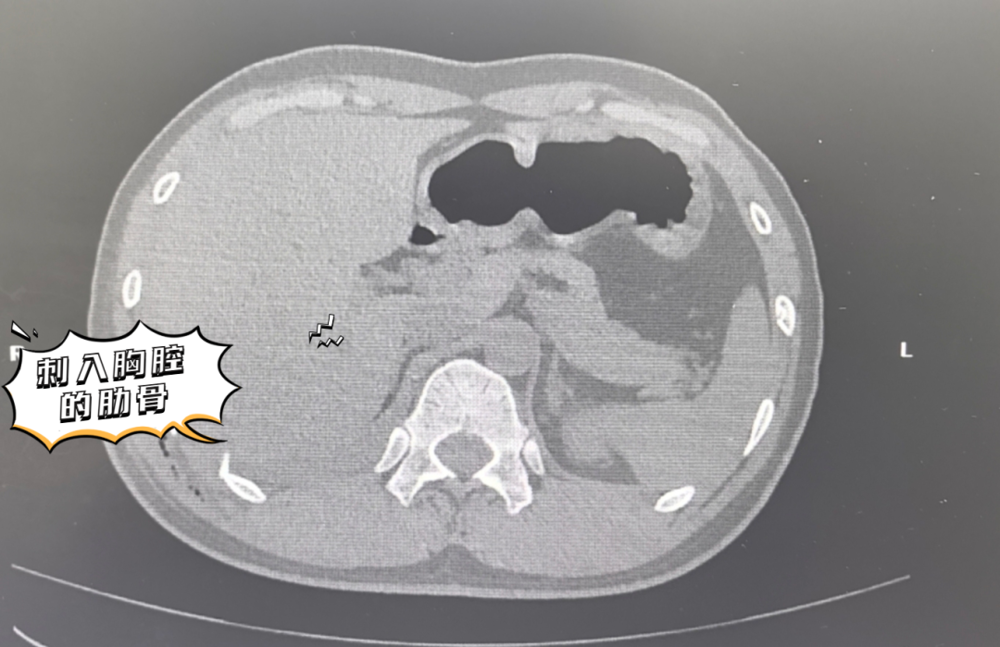

手术由金根标主任主刀,术中探查所见触目惊心:胸腔内积血超过2000ml,断裂的肋骨残端如同利刃,刺破了肋间血管及膈肌上动脉,造成汹涌的活动性出血,同时肺组织也存在撕裂伤。